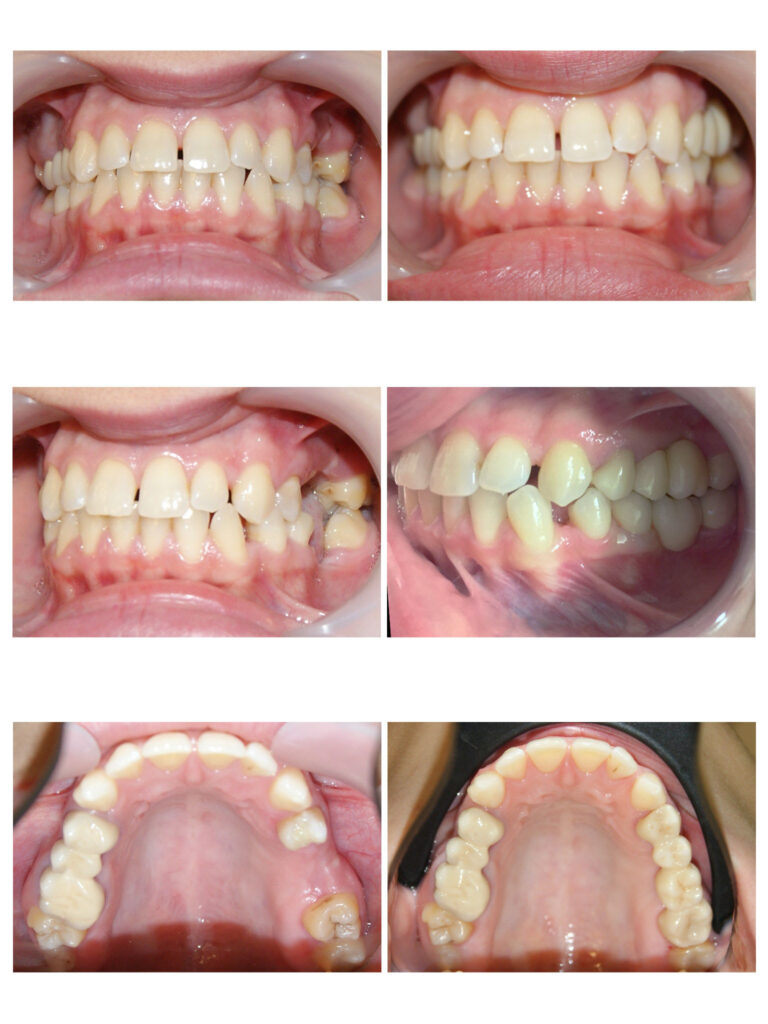

Crearea spațiului pentru alinierea dinților și pentru corectarea mușcăturii încrucișate.

Corectarea angulațiilor dentare și a mușcăturii

Îndreptarea axelor dentare are un efect semnificativ atât asupra dinților cât și asupra țesuturilor de susținere

Pozițiile copiilor în somn (cu pumnul sub obraz) timp îndelungat poate determina dezvoltarea asimetrică a oaselor maxilare. Așa cum se vede în poze, cu ajutorul aparatelor ortodontice fixe am îndreptat axele dentare

În cazul de față ortodonția ne-a ajutat să oferim lărgime semnificativă zâmbetului și să prevenim retracțiile gingivale de pe caninii inferiori prin distalizare.